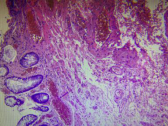

內痔位于齒狀線以上,是直腸上靜脈叢曲張的結果。外痔是直腸下靜脈叢曲張所致,位于齒狀線以下。由于直腸上、下靜脈叢間有豐富的吻合支,其中一個靜脈叢的曲張變化可波及另一靜脈叢,從而導致內、外痔合并發生,形成混合痔。鏡下,外痔表明由鱗狀上皮被覆,內痔則覆以柱狀上皮,其下主要由擴張、薄壁而充滿血液的靜脈組成,靜脈內常有血栓形成。此外,可見多少不等的漿細胞、淋巴細胞和中性粒細胞浸潤,表面可有潰瘍形成。

外痔 內痔 混合痔